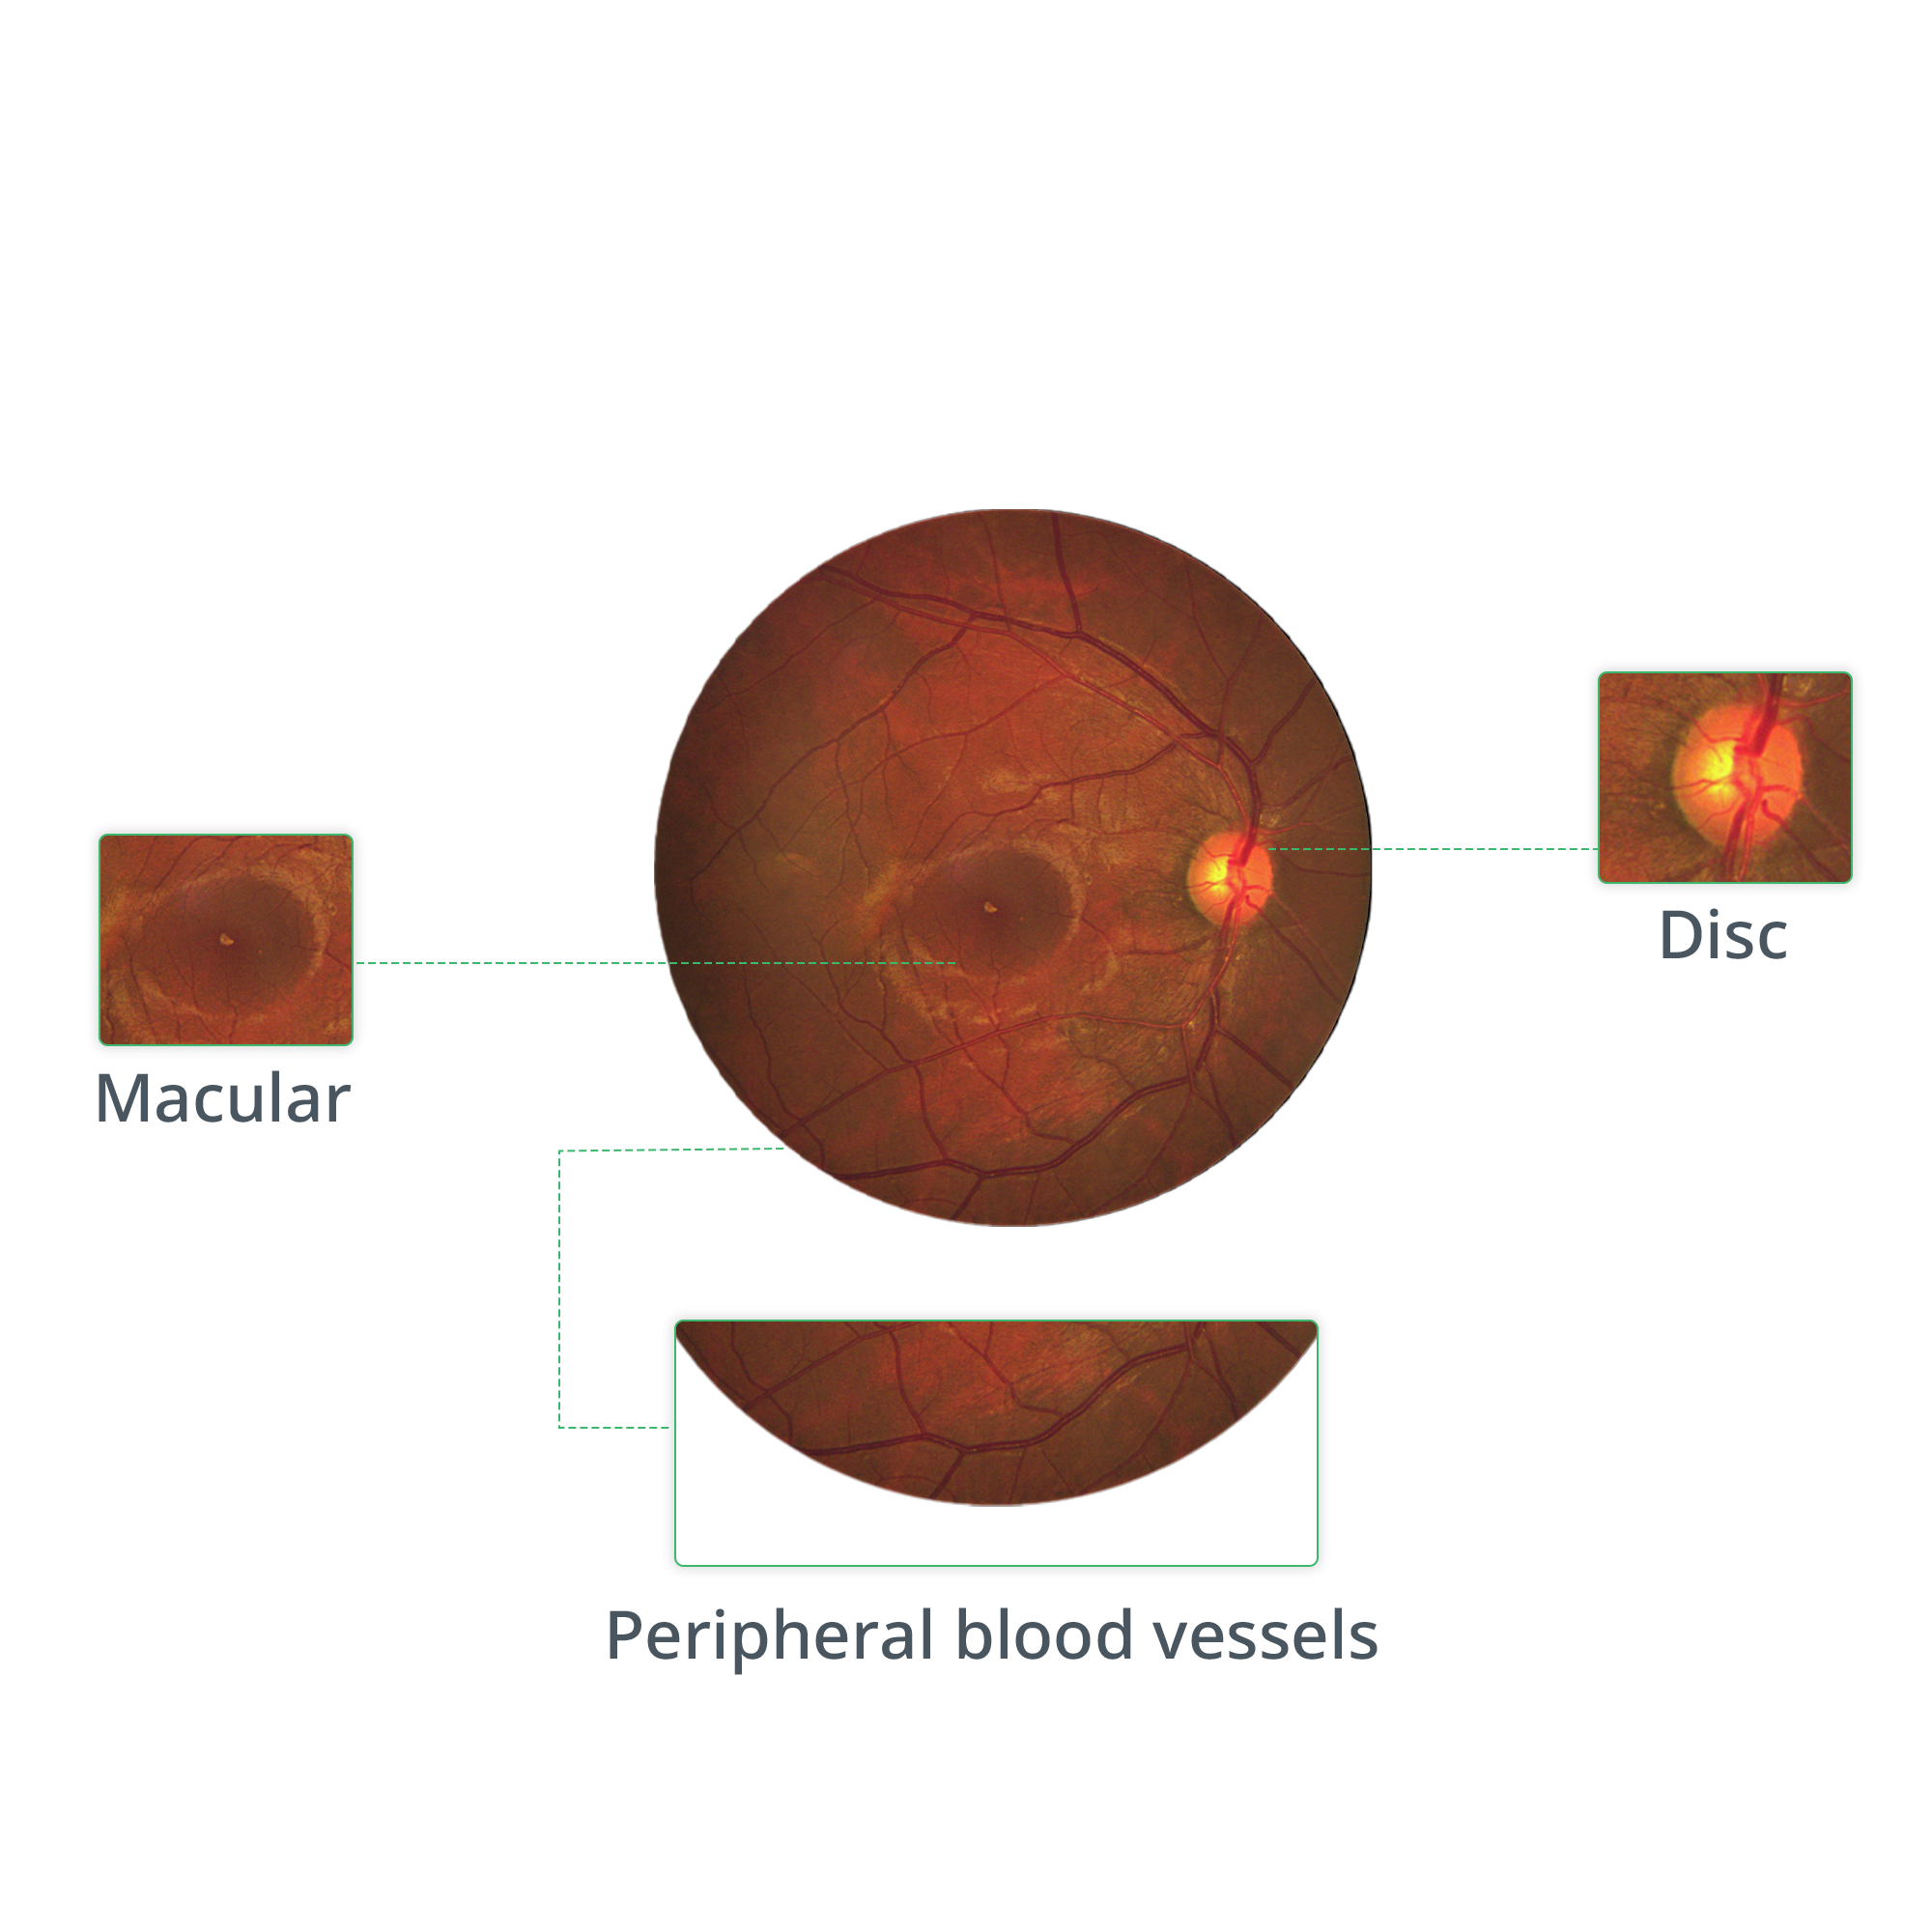

Handheld, non-mydriatic fundus imaging with a clear view of the posterior pole in a single shot.

Delivering crystal-clear, high contrast retinal images with a 45° field of view in single shot, and montage to reach the periphery.

Providing retinal images with 2 different imaging modalities

Imaging modalities

TrueColor, Red-Free Retinal Imaging